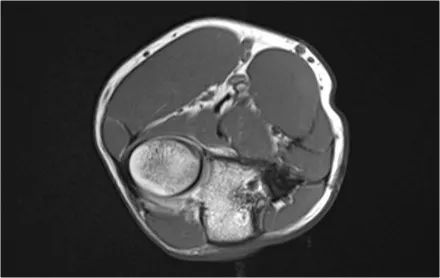

然后执行OATS程序。OATS代表骨软骨自体移植,从一些其他非承重骨中取出软骨和骨头,并转移到肱骨小头。在该患者中,软骨取自膝盖的非承重部分。

然后在肱骨小头孔钻和用自体骨和软骨填充缺陷。,在这里,在肱骨小头的孔填充有四块骨头和软骨。肱骨小头的对侧是桡骨头。